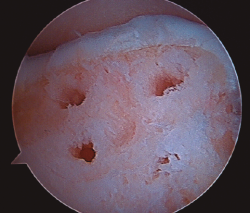

Figura 6. Empleo de impactador para la medición de la lesión y uso de la trefina de la zona donante.

- Extracción de un cilindro osteocondral de la zona receptora de una profundidad de 15 mm y grosor dependiendo del tamaño de la lesión. Existen impactadores para compactar el hueso esponjoso subcondral (Figura 5).

- Intercambio de portales para asegurar la correcta realización del túnel (Figura 6).